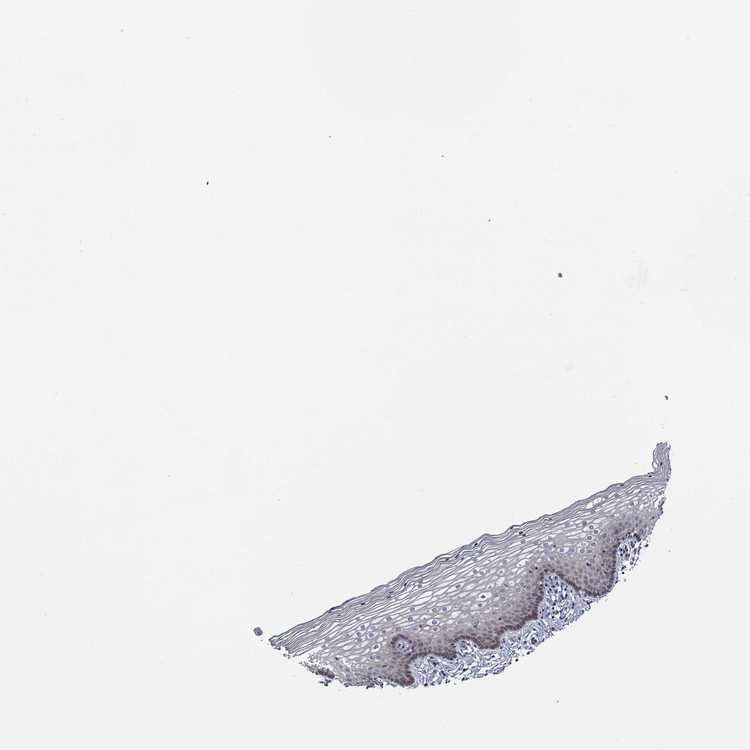

TISSUE PRIMARY DATA VAGINA Show tissue menu

VAGINA - Antibody stainingi

Antibody staining in the annotated cell types in the current human tissue is reported as not detected, low, medium, or high, based on conventional immunohistochemistry profiling in selected tissues. This score is based on the combination of the staining intensity and fraction of stained cells.

Each image is clickable and will lead to virtual microscopy that enables deeper exploration of all samples and also displays staining intensity scores, fraction scores and subcellular localization as well as patient and tissue information for each sample.

Antibody HPA036503Antibody HPA064387Antibody HPA076072Antibody CAB020784

Squamous epithelial cells Not detectedNot detectedLowHigh